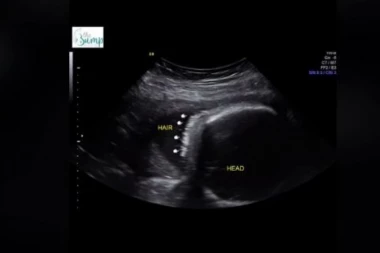

Žena 16:40 14.01.2024 NA ULTRAZVUKU SU PRIMETILI ČUDNE TAČKICE: Majka zanemela od ŠOKA kada su joj lekari saopštili šta je TO!

Žena 15:30 10.01.2024 KADA JE OTIŠLA NA ULTRAZVUK ŠOKIRANO JE GLEDALA U OVU TAČKU: Zbunjena mama je na pregledu saznala šta je to, BACA U NEVERICU (VIDEO)